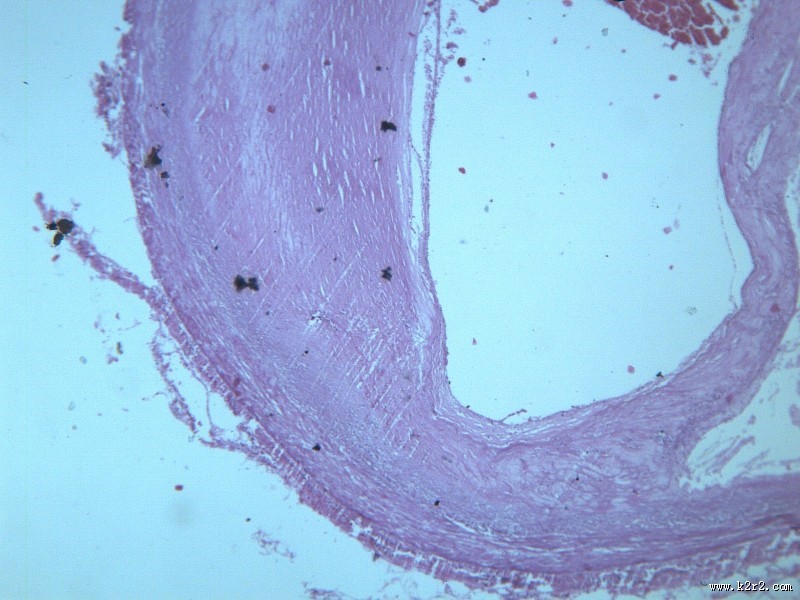

首页 > 其他类别 > 动脉粥样硬化(12张) > 动脉粥样硬化 第4张

动脉粥样硬化 - 第4张